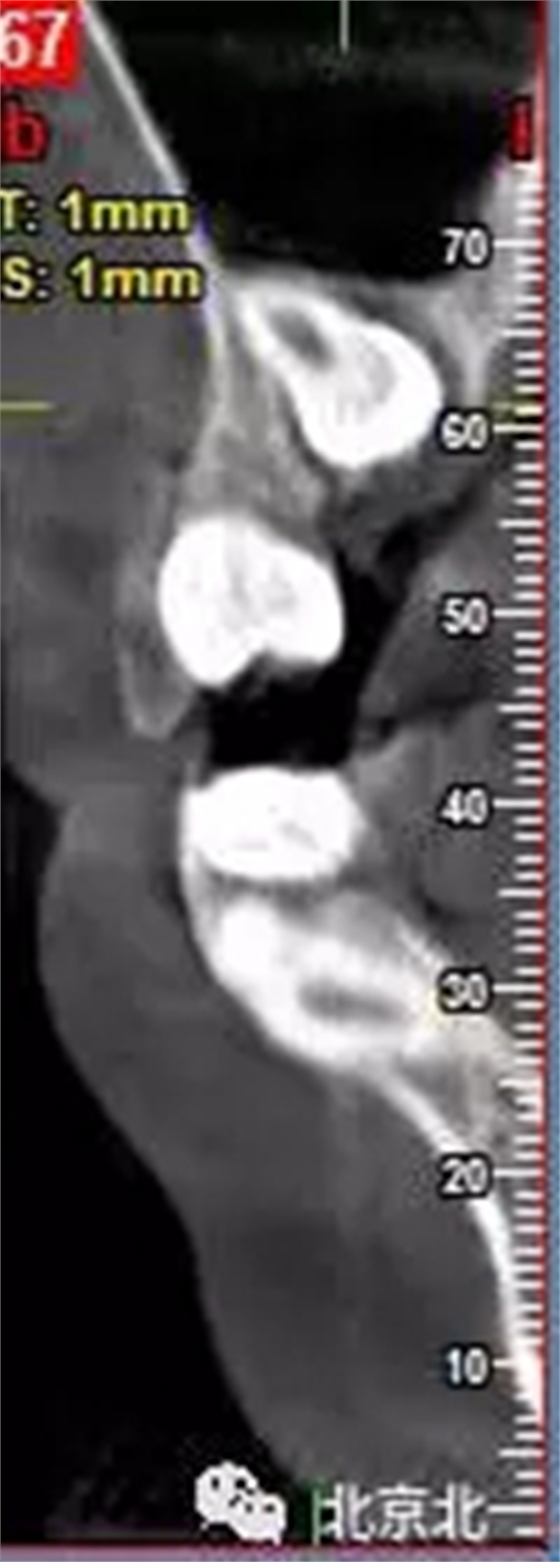

圖一:拔牙前影像片(CBCT)